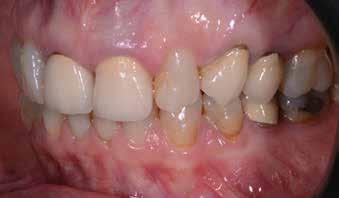

A 26 éves férfi páciens azzal a kéréssel kereste fel a rendelőnket, hogy a frontfogai esztétikusabb megjelenését szeretné elérni. A páciens jó általános egészségi állapottal rendelkezett, nem szenvedett allergiáktól és nem kellett rendszeresen gyógyszereket szednie. A páciens lehetőség szerint kerülte a fogai megmutatását. Rendkívül zavarónak találta a nagymetszői között, a középvonalnak megfelelően látható rést, a fogain látható kopási jeleket, valamint a fogai méretét is túl kicsinek találta. A szájüregi vizsgálat során megállapítottuk, hogy a nagymetsző fogai (11, 21) élharapásban vannak, valamint az alsó fogíven kismértékű torlódást észleltünk. A felső frontfogakon

(13-23) attrícióra utaló jeleket találtunk. A fogak kopása a nagymetszőfogaknak megfelelően volt a legkifejezettebb (1. ábra) . Az előbbiekben említett fogak (11, 21) ezen kívül némileg elfordultak, és jelentősebb méretű diasztéma volt köztük. A páciens Angle I.-osztályú állcsontrelációs helyzettel rendelkezett. A vizsgálat során feltűnt, hogy a páciens csak nagyon óvatosan mert mosolyogni (2. ábra)

A szájüregi vizsgálat során nem találtunk szuvas léziók jelenlétére utaló eltéréseket. A nagymetszőfogakon megfigyelhető jelentős mértékű kopás ellenére nem észleltünk craniomandibuláris diszfunkció jelenlétére utaló jeleket. A vizsgálat befejezését követően a pácienst tájékoztattuk a különböző kezelési lehetőségekről. Az esztétikai megjelenés javítása érdekében először egy alignerekkel végzett fogszabályzó kezelés elvégzését, majd a harapási helyzet optimalizálását követően a felső frontfogai kompozittal történő direkt felépítését vagy héjakkal történő ellátását (pl.: non-prep héjak) javasoltuk (3. és 4. ábra).